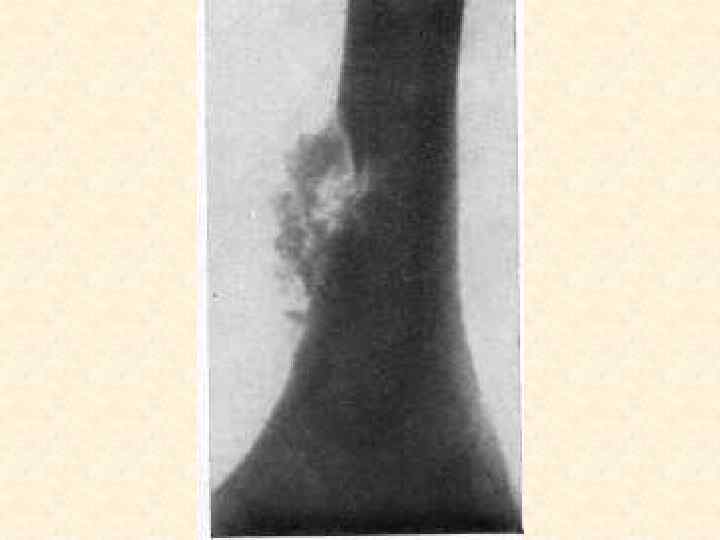

Заболевания, поражающие костную систему • • • Остеомиелит, артрит Артроз Остеопороз Остеомы Переломы костей

Методы диагностики поражения опорной системы человека 1. 2. 3. 4. Рентген, КТ, Радиоизотопная диагностика, Остеоденситометрия